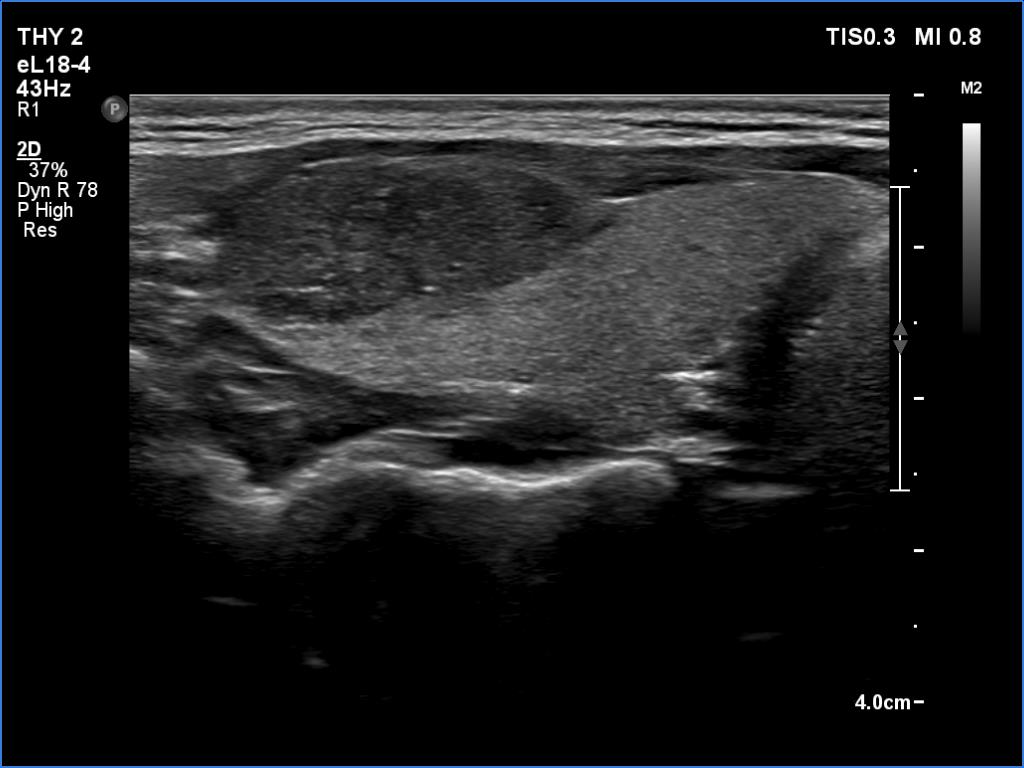

Ultrasonography. The thyroid was echonormal and presented two discrete lesions in the right lobe. The larger, upper one showed irregular margins, abutting and bulging contours and had back wall figures. The intranodular vascularization was significantly increased. The smaller lesion had microcalcifications and presented taller-than-wide shape.

Comment. It is worth thoroughly analyzing the intranodular echogenic figures. These are partly linear and most of them are related to tiny ventral cystic areas.